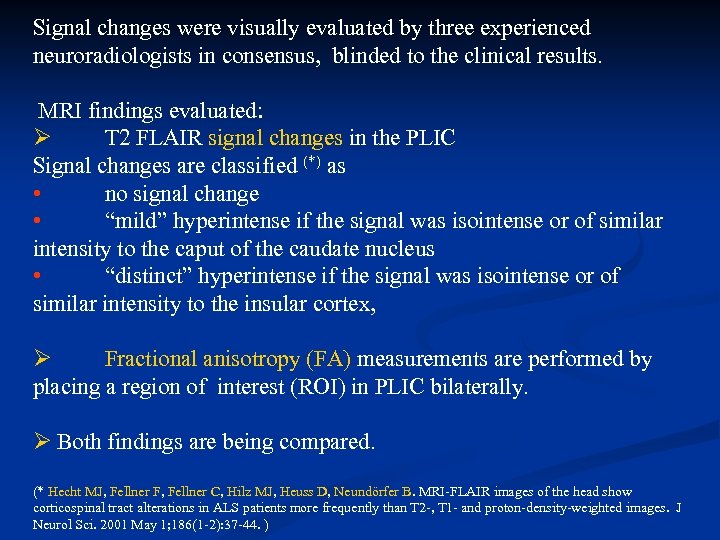

Signal changes were visually evaluated by three experienced neuroradiologists in consensus, blinded to the clinical results. MRI findings evaluated: T 2 FLAIR signal changes in the PLIC Signal changes are classified (*) as • no signal change • “mild” hyperintense if the signal was isointense or of similar intensity to the caput of the caudate nucleus • “distinct” hyperintense if the signal was isointense or of similar intensity to the insular cortex, Fractional anisotropy (FA) measurements are performed by placing a region of interest (ROI) in PLIC bilaterally. Both findings are being compared. (* Hecht MJ, Fellner F, Fellner C, Hilz MJ, Heuss D, Neundörfer B. MRI-FLAIR images of the head show corticospinal tract alterations in ALS patients more frequently than T 2 -, T 1 - and proton-density-weighted images. J Neurol Sci. 2001 May 1; 186(1 -2): 37 -44. )

Signal changes were visually evaluated by three experienced neuroradiologists in consensus, blinded to the clinical results. MRI findings evaluated: T 2 FLAIR signal changes in the PLIC Signal changes are classified (*) as • no signal change • “mild” hyperintense if the signal was isointense or of similar intensity to the caput of the caudate nucleus • “distinct” hyperintense if the signal was isointense or of similar intensity to the insular cortex, Fractional anisotropy (FA) measurements are performed by placing a region of interest (ROI) in PLIC bilaterally. Both findings are being compared. (* Hecht MJ, Fellner F, Fellner C, Hilz MJ, Heuss D, Neundörfer B. MRI-FLAIR images of the head show corticospinal tract alterations in ALS patients more frequently than T 2 -, T 1 - and proton-density-weighted images. J Neurol Sci. 2001 May 1; 186(1 -2): 37 -44. )